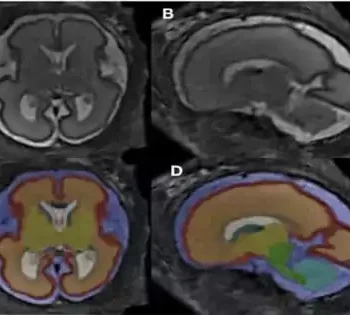

Researchers discovered significant changes in the brain structure of fetuses exposed to alcohol compared to healthy controls in the first MRI-based study of pre-natal alcohol exposure. The study's findings were